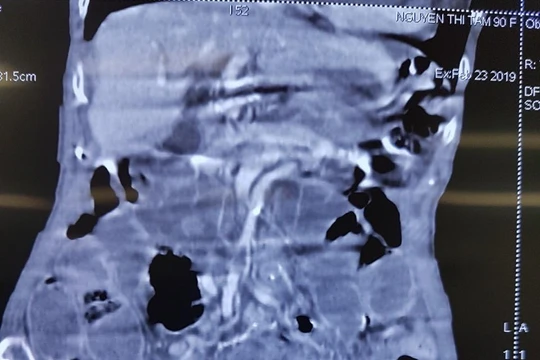

Hình ảnh chụp CT của bệnh nhân

Cứu sống cụ bà 90 tuổi bị thủng ruột do bệnh lý hiếm gặp

VietTimes - Các bác sỹ của Bệnh viện Trung ương Quân đội 108 vừa phẫu thuật cứu sống một cụ bà 90 tuổi bị thủng ruột do thoát vị bịt– một bệnh lý hiếm gặp và nguy hiểm. Chỉ sau 5 ngày được cấp cứu, bệnh nhân đã ổn định và hôm nay, 22/4, đã được ra viện.